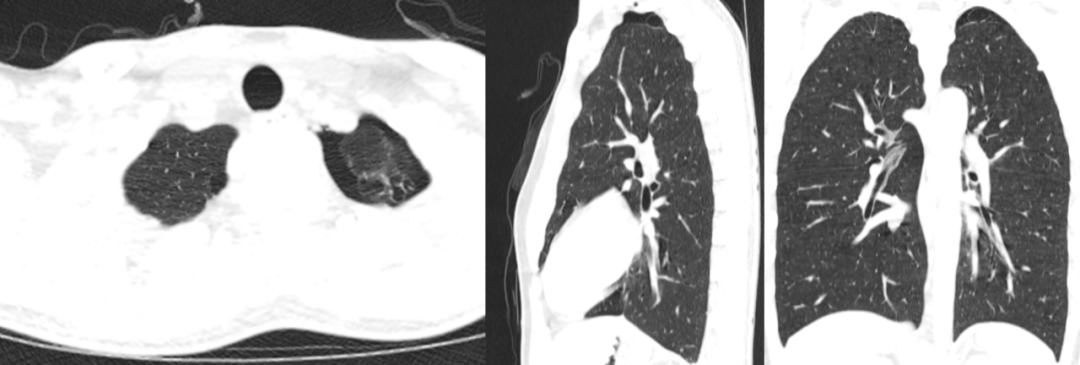

病例2

• 男,34岁

• 主诉:左侧背部疼痛一个半月

• 现病史:患者一个半月前无明显诱因下出现左侧背部疼痛,无明显放射痛,无明显加重或缓解因素。无胸闷气喘、无咳嗽咳痰、无呼吸困难,无腹痛腹泻,无恶心呕吐,无发热寒战患者遂至外院就诊,查 PET/CT 示:1、左侧第6后肋 3.3×1.6cm 骨质破坏区,外形呈包壳样,骨皮质不连续,周围软组织及胸膜增厚,FDG 代谢增高,考虑左侧第6后肋恶性骨肿瘤伴病理性骨折可能性大

• 影像检查:2022-02-09 胸部CT平扫;影像号:2423095

影像学表现

图片